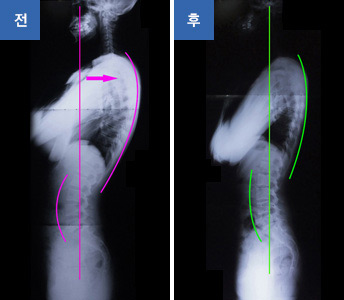

ÀúÈñ °³²¼öÀçȰÀÇÇаú ÀÚ¼¼Ã¼Çü±³Á¤ Ŭ¸®´ÐÀº ƯÈ÷ ±ÁÀº µîÀ̳ª ±ÁÀº ¾î±ú (ÀÏ¸í ¶ó¿îµå ¼ñ´õ : Round shoulder), °ÅºÏ¸ñ ¶Ç´Â ÀÚ¶ó¸ñ, ¿À¸®±ÃµÀÌ, ÀÏÀÚÇ㸮, ÆíÆòµîÁõÈıº, »óºÎ±³Â÷ÁõÈıº ¶Ç´Â ÇϺα³Â÷ÁõÈıº µîÀÇ Æ¯È÷ ôÃßÀÇ Ãø¸é¿¡¼ÀÇ ¸¸°î°ú °ü·ÃµÈ ±³Á¤À» ÁÖ·Î ÇÏ°Ô µË´Ï´Ù.

°³²¼ö(â³)ÀçȰÀÇÇаúÀÇ ÀÚ¼¼Ã¼Çü±³Á¤ÀÇ Ä¡·á´Â Á¤È®ÇÑ Áø´ÜÀ» ÇÙ½ÉÀ¸·Î ±×¿¡ ¸Â´Â Àüü Ä¡·áÁøµéÀÇ ÆÀ¿öÅ©·Î ¸¸µé¾î³ª°©´Ï´Ù.

ÀçȰÀÇÇаú Àü¹® µµ¼öÄ¡·á¿ä¹ý°ú ¿îµ¿Ã³¹æÀ» ÅëÇÑ ÁßÀå±âÀûÀÎ Ç÷£À» Â¥¸ç ÇöÀçÀÇ ÅëÁõÄ¡·á ¿ª½Ã Àü¹®ÅëÁõŬ¸®´ÐÀ¸·Î ÇØ°áÇØ³ª°¡´Â ¹æ½ÄÀÔ´Ï´Ù.

µµ¼öÄ¡·á¸¦ Á¤ÅëÀ¸·Î À̼öÇÑ Àü¹®ÀÇ ¹× Àü¹®Ä¡·á»çÀÇ ´Ù°¢ÀûÀÎ µµ¼ö ±³Á¤Ä¡·á¿Í ÷´ÜÀÇ·áÀåºñ¸¦ ÅëÇÑ Ä¡·á, ¹êµå³ª ½½¸µ µîÀÇ ÀÏ»ó»ýȰ ¼Ó¿¡¼ ´Ù¾çÇÑ ¼Òµµ±¸µéÀ» ÀÌ¿ëÇÑ ±³Á¤Ä¡·á ±×¸®°í Áß, Àå±âÀûÀ¸·Î´Â À߸øµÈ ÀÚ¼¼¿¡ ´ëÇÑ ÀÎÁö¿Í ¹Ù¸¥ÀÚ¼¼±³À°»Ó¸¸ÀÌ ¾Æ´Ï¶ó ¸öÀÇ ¹ß¶õ½ºÀÇ Ç×»ó¼ºÀ» À¯ÁöÇϰí ôÃß¿Í °ñ¹ÝÀ» ¾ÈÁ¤È½ÃÄÑ ±Ùº»ÀûÀ¸·Î ¿Ã¹Ù¸¥ ÀÚ¼¼¿Í ôÃ߰ǰÀ» À¯ÁöÇÒ ¼ö ÀÖ´Â ÀúÈñ º´¿ø¸¸ÀÇ °³²¼ö(â³) ÄÚ¾î¿îµ¿ ½Ã½ºÅÛÀ» ÅëÇÑ ±³Á¤Ä¡·á ÇÁ·Î±×·¥À» À̼öÇÏ½Ç ¼ö ÀÖ°Ú½À´Ï´Ù.